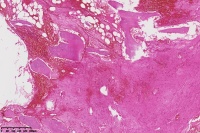

右胫骨内组织,单纯性骨囊肿?

性别

男

年龄

12岁

临床诊断

内生性软骨瘤?骨囊肿?

标本名称

右胫骨内组织

图4